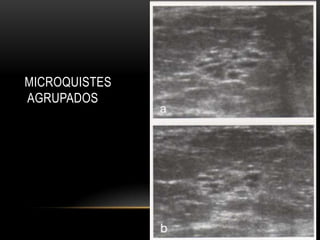

MICROQUISTES

AGRUPADOS

• Quiste complicado no palpable, quiste complejo y cumulo de